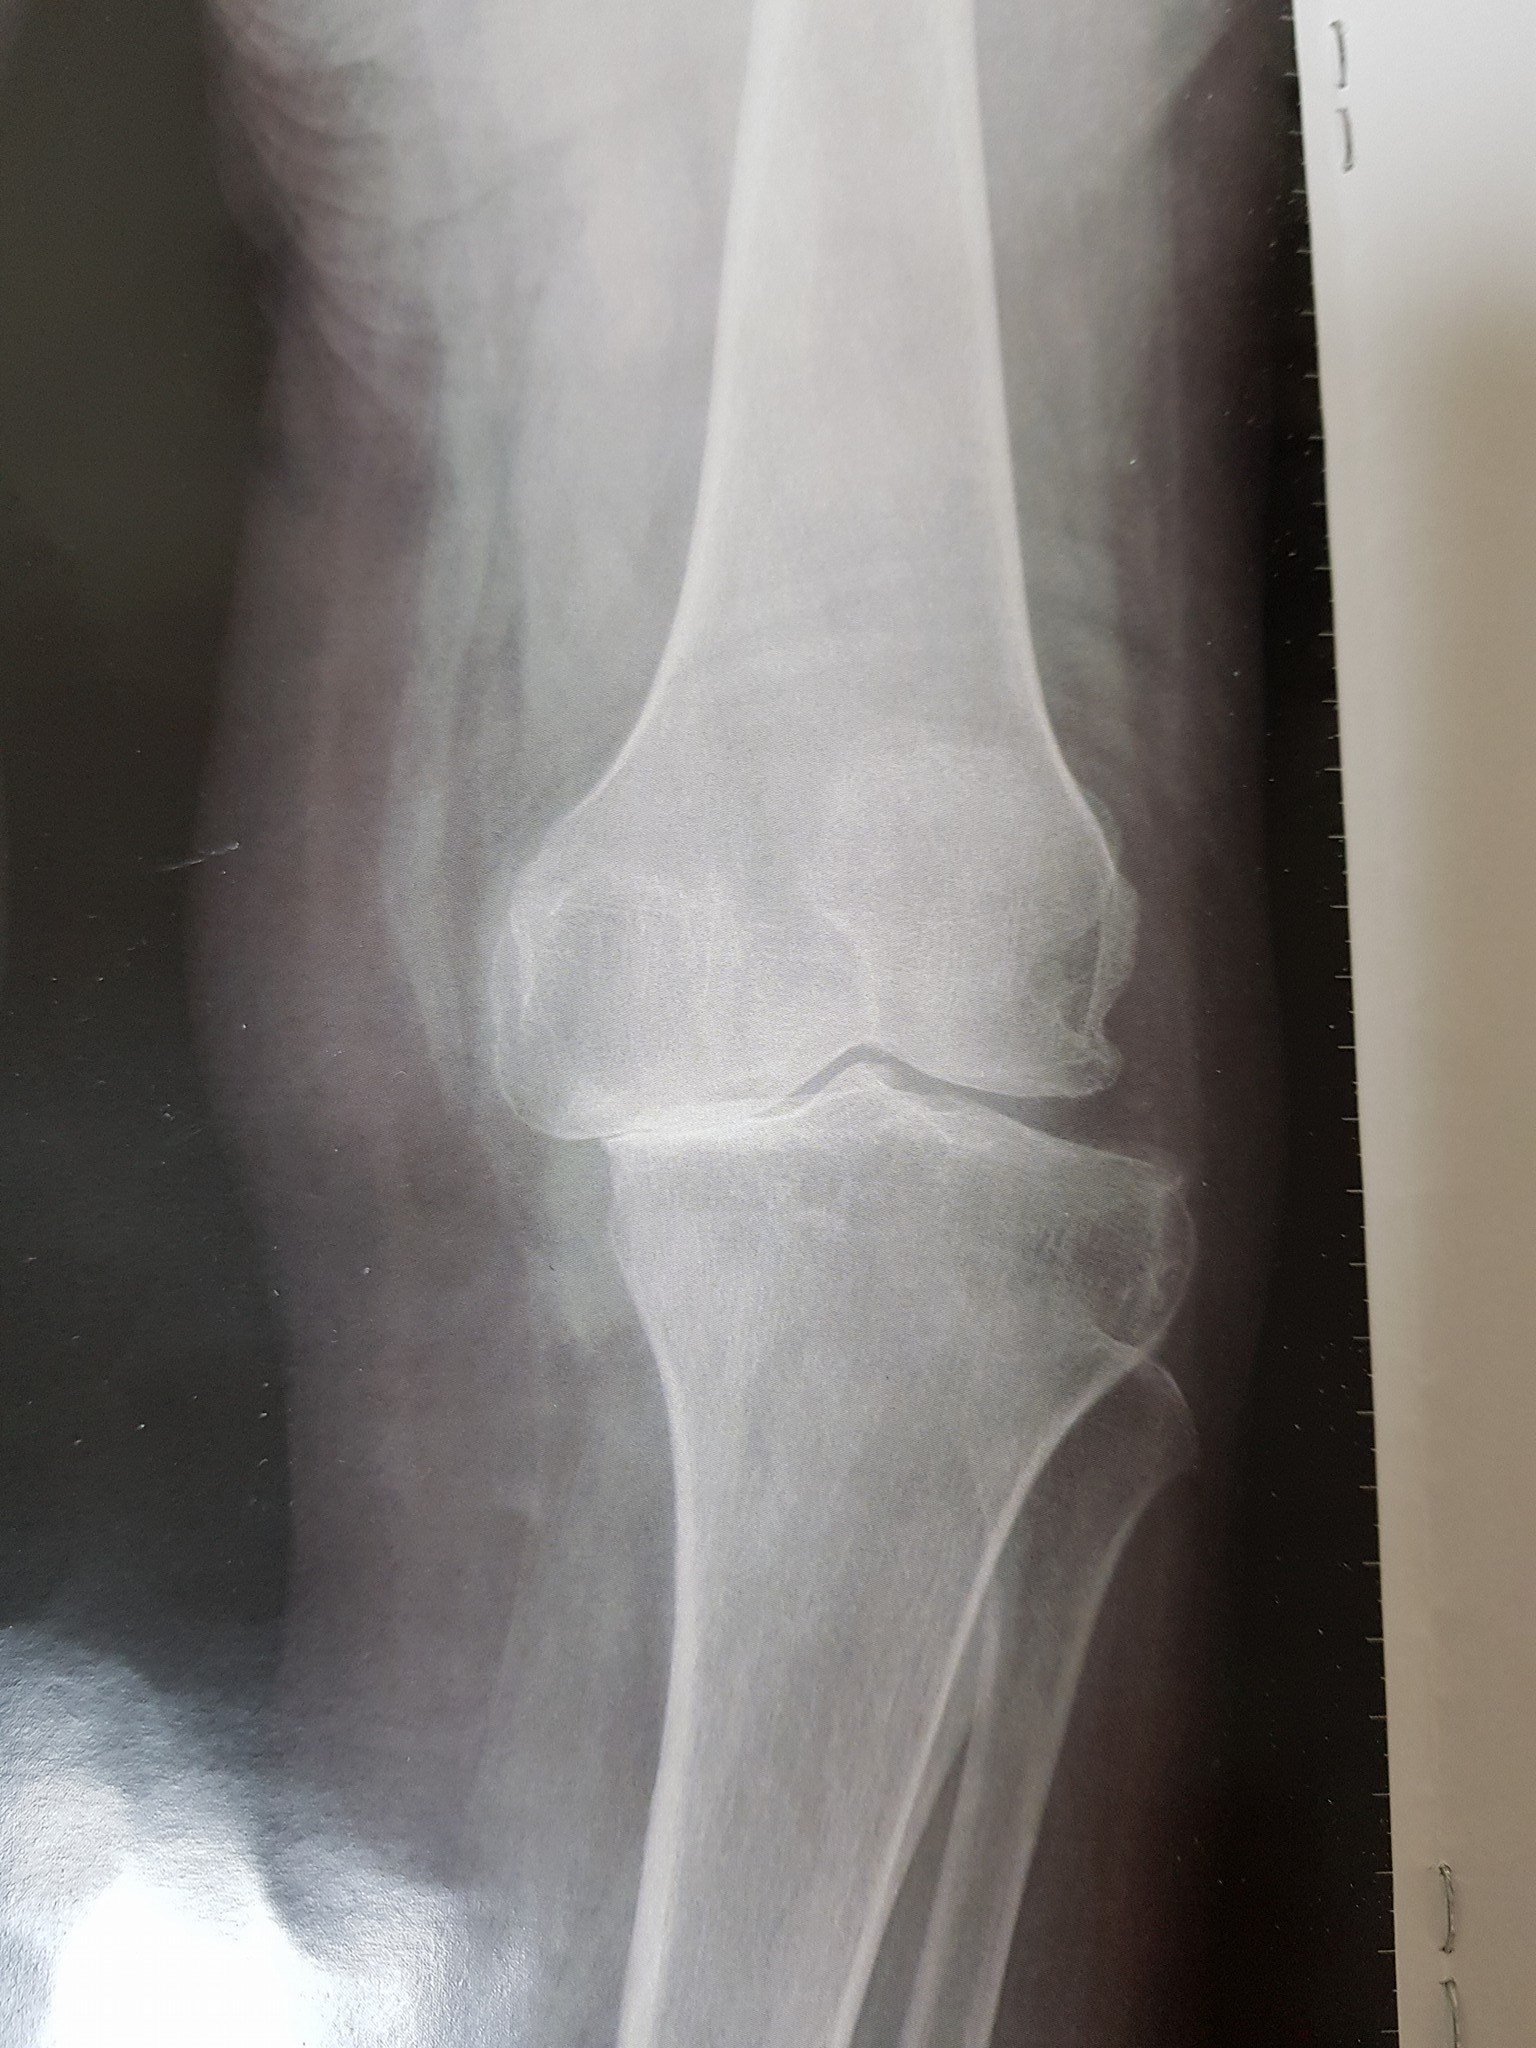

جراحة العظام والمفاصل

كافة انواع الكسور وعلاجها